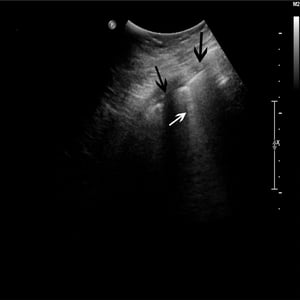

Comet Tail Artifact

Sonographic "comet tail artifact" (white arrow) inferior to rib (black arrows) on thoracic ultrasound. Comet tail artifact corresponds to the radiographic finding of Kerley B lines.

© 2017 Elliot K. Fishman, MD.